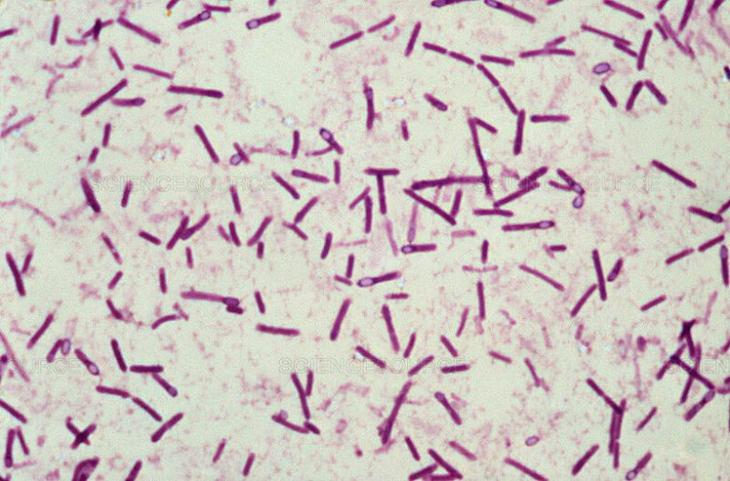

1. Clostridium botulinum

Эта бактерия вызывает ботулизм — тяжелое заболевание, поражающее нервную систему человека. Больные ботулизмом погибают, как правило, от паралича дыхательной мускулатуры и последующей гипоксии. Считается, что чайной ложки ботулины достаточно, чтобы уничтожить население США. А 4 кг хватит на истребление всех жителей планеты.

5. Clostridium tetani, или столбнячная палочка

Эта бактерия обитает в безвоздушной среде, а в иных условиях образует защитные споры. В глубоких ранах палочка развивается очень активно, поэтому именно так и происходит заражение столбняком. В результате столбнячный токсин поражает нервную систему человека, вызывая длинные и мучительные судороги. При этом человек испытывает страх и сильную боль во всем теле. Затруднение в открывании рта приводит к голоданию и обезвоживанию. Смертность от столбняка даже при лечении колеблется от 40 до 70%.